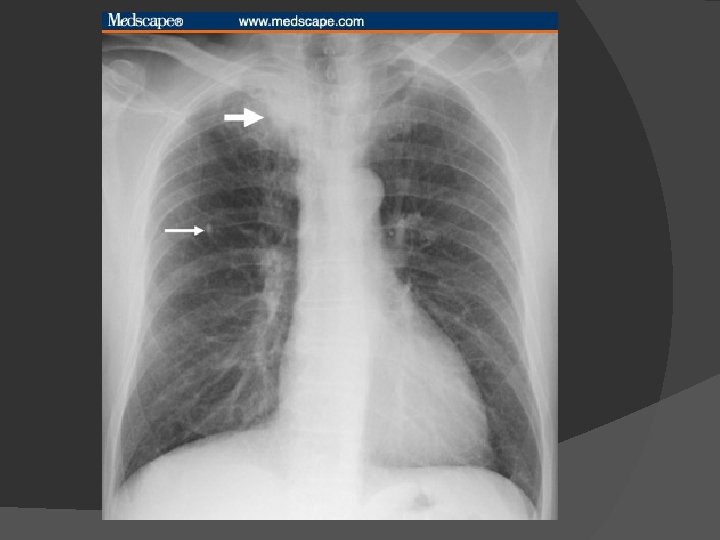

Signs, Symptoms and Diagnosis of TB X-ray • Sputum smear • microscopy Culture •

Diagnosis of pulmonary TB Sputum smear Acid fast stain (>10, 000 CFU/ml) Bronchoscopy Chest X-Ray Tuberculin skin testing (TST) National Cancer Institute. 2006 http: //www. nlm. nih. gov/medlineplus/ency/images/ency/fullsize/1607. jpg TMC 207: slide 29